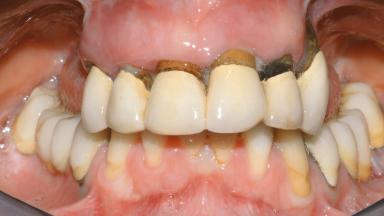

Conventional Loading of Eight Implants in the Maxilla and Final Restoration with a Full-Arch Gold-Ceramic FDP

A 35-year-old Caucasian female presenting with advanced periodontal disease involving both the maxillary and the mandibular dentition was referred for evaluation. The patient, a non-smoker in good general health, requested treatment for recurrent periodontal abscesses, tooth mobility, and discomfort during chewing, as well as restoration of her missing teeth with a fixed prosthesis to improve mastication and esthetics. All residual maxillary teeth exhibited plaque deposits, deep pockets, bleeding on probing, and class III mobility and were evaluated as hopeless. All residual mandibular teeth except tooth 37 could be maintained after periodontal therapy.

| Prosthesis Type | FDP |

| Defining Characteristics | Fully edentulous upper jaw to be rehabilitated with an implant-borne fixed dental prosthesis |

| Retention | Cemented, with prosthesis margin < 3mm submucosal Cemented, with prosthesis margin < 3mm submucosal |